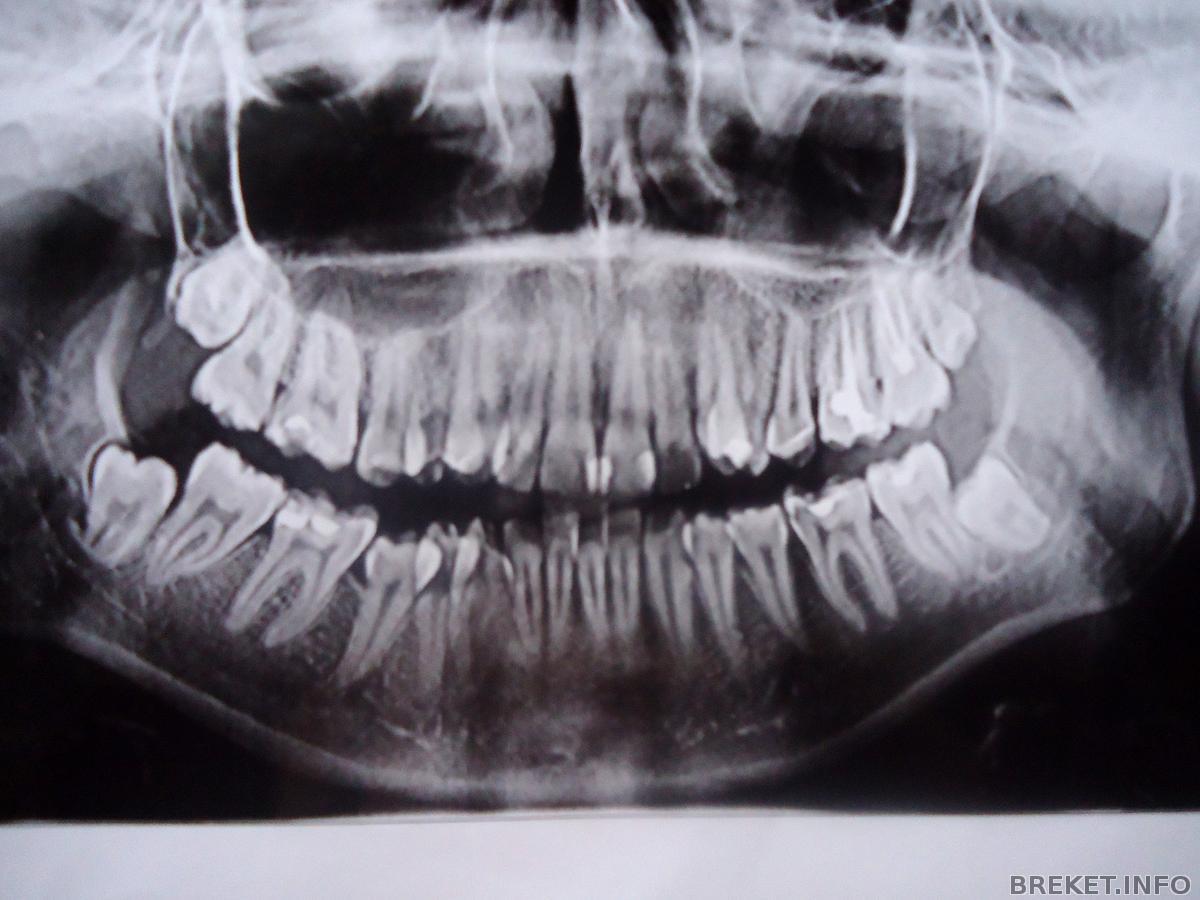

на фотке правый сверху удалила

Планирую следующим удалить на фотке правый снизу. Он стремный какой-то.